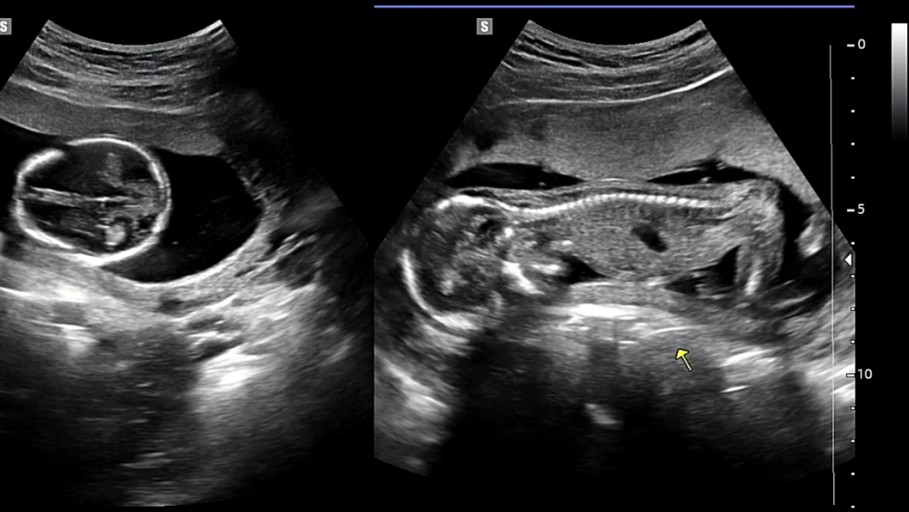

현재 의료법 제20조 2항은 임신 32주 이전에 의료인이 태아의 성별을 알려줄 수 없도록 규정하고 있었습니다. 이는 남아 선호 사상에 기인한 여아 낙태 예방을 위한 조항으로 설계되었습니다.

그러나 이번 결정은 2008년 헌법재판소의 이전 판결을 재확인한 것입니다. 그 판결에 따라 국회는 2009년에 관련 법을 개정하여 임신 32주부터 성별을 알려줄 수 있도록 허용했습니다.